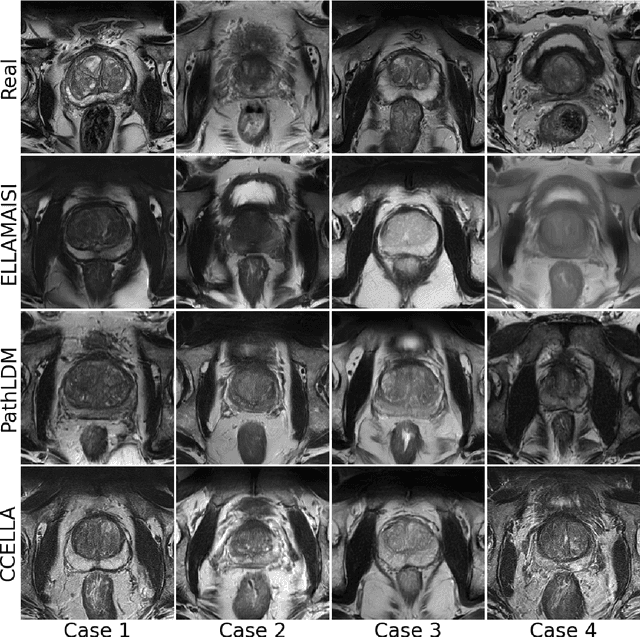

Abstract:Objective: Latent diffusion models (LDMs) could mitigate data scarcity challenges affecting machine learning development for medical image interpretation. The recent CCELLA LDM improved prostate cancer detection performance using synthetic MRI for classifier training but was limited to the axial T2-weighted (AxT2) sequence, did not investigate inter-institutional domain shift, and prioritized radiology over histopathology outcomes. We propose CCELLA++ to address these limitations and improve clinical utility. Methods: CCELLA++ expands CCELLA for simultaneous biparametric prostate MRI (bpMRI) generation, including the AxT2, high b-value diffusion series (HighB) and apparent diffusion coefficient map (ADC). Domain adaptation was investigated by pretraining classifiers on real or LDM-generated synthetic data from an internal institution, followed with fine-tuning on progressively smaller fractions of an out-of-distribution, external dataset. Results: CCELLA++ improved 3D FID for HighB and ADC but not AxT2 (0.013, 0.012, 0.063 respectively) sequences compared to CCELLA (0.060). Classifier pretraining with CCELLA++ bpMRI outperformed real bpMRI in AP and AUC for all domain adaptation scenarios. CCELLA++ pretraining achieved highest classifier performance below 50% (n=665) external dataset volume. Conclusion: Synthetic bpMRI generated by our method can improve downstream classifier generalization and performance beyond real bpMRI or CCELLA-generated AxT2-only images. Future work should seek to quantify medical image sample quality, balance multi-sequence LDM training, and condition the LDM with additional information. Significance: The proposed CCELLA++ LDM can generate synthetic bpMRI that outperforms real data for domain adaptation with a limited target institution dataset. Our code is available at https://github.com/grabkeem/CCELLA-plus-plus

Abstract:Latent diffusion models (LDM) could alleviate data scarcity challenges affecting machine learning development for medical imaging. However, medical LDM training typically relies on performance- or scientific accessibility-limiting strategies including a reliance on short-prompt text encoders, the reuse of non-medical LDMs, or a requirement for fine-tuning with large data volumes. We propose a Class-Conditioned Efficient Large Language model Adapter (CCELLA) to address these limitations. CCELLA is a novel dual-head conditioning approach that simultaneously conditions the LDM U-Net with non-medical large language model-encoded text features through cross-attention and with pathology classification through the timestep embedding. We also propose a joint loss function and a data-efficient LDM training framework. In combination, these strategies enable pathology-conditioned LDM training for high-quality medical image synthesis given limited data volume and human data annotation, improving LDM performance and scientific accessibility. Our method achieves a 3D FID score of 0.025 on a size-limited prostate MRI dataset, significantly outperforming a recent foundation model with FID 0.071. When training a classifier for prostate cancer prediction, adding synthetic images generated by our method to the training dataset improves classifier accuracy from 69% to 74%. Training a classifier solely on our method's synthetic images achieved comparable performance to training on real images alone.